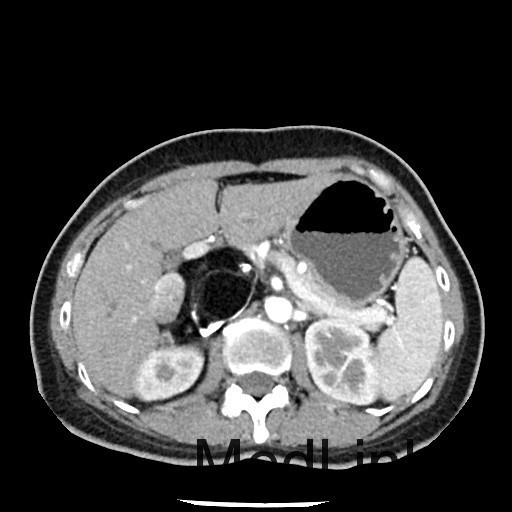

查体:神清,一般情况好,无水牛背、满月脸,皮肤无紫纹。 辅查:全腹CT平扫+增强提示右侧腹膜后区占位性病变,畸胎瘤可能性大。

讨论:本例畸胎瘤因发生在肾上腺区,因此表现为发作性高血压。一般只要在CT图像上看到钙化、脂肪密度等特征性征象,增强扫描实性成分轻度强化,畸胎瘤的诊断一般不难。不过非成熟性的畸胎瘤一般缺少钙化和脂肪成分,此时要与腹膜后其他来源的实性肿瘤相鉴别。本例病理大体能够看到毛发,也是畸胎瘤比较特征性的病理表现。